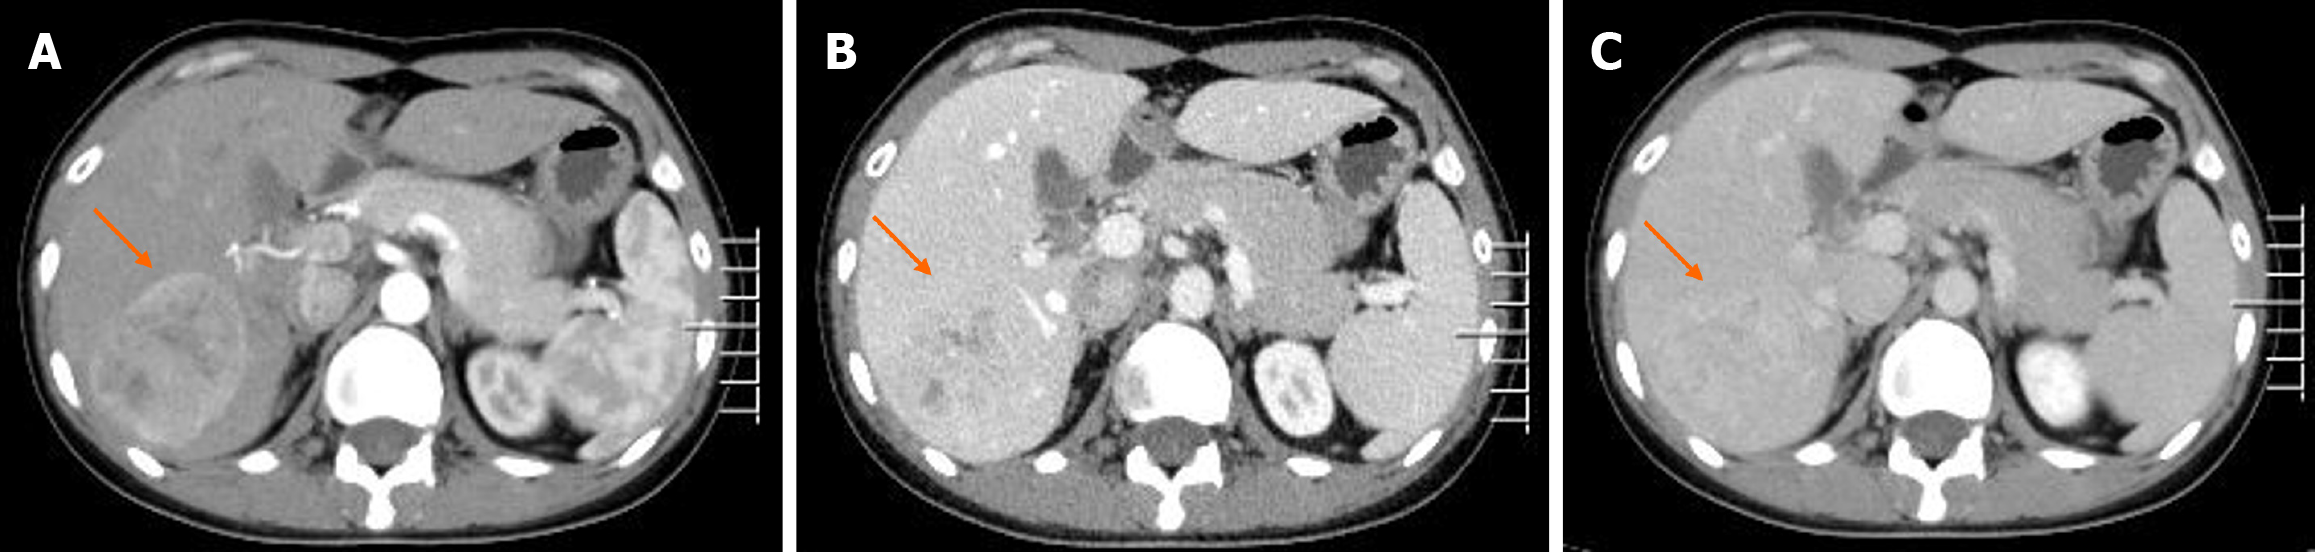

Figure 1 Images of the first contrast-enhanced computed tomography.

A: The lesion demonstrated significant enhancement in the arterial phase; B and C: Slightly higher enhancement in the portal vein and delayed phases compared to the hepatic parenchyma.